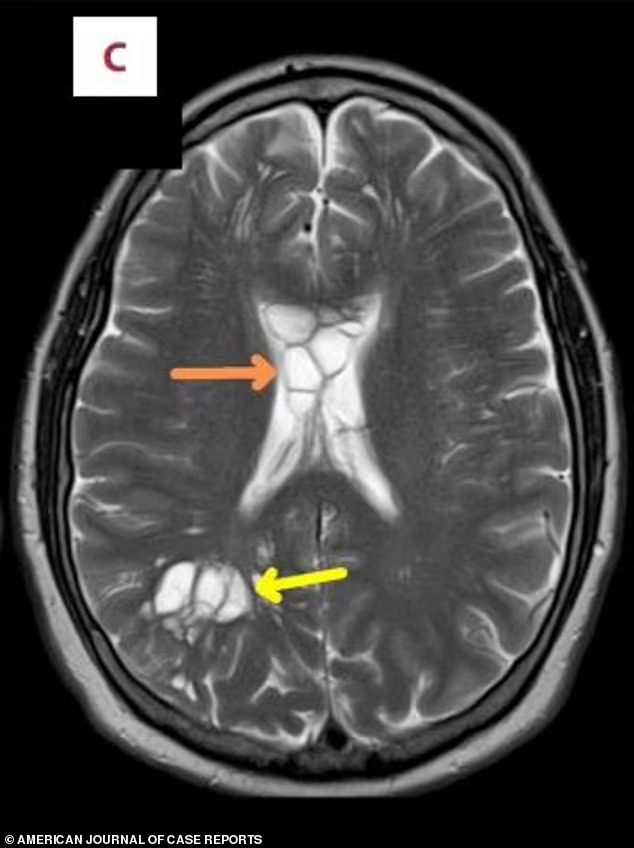

On Friday, Dailymail reported that scans showed several cysts and inflammation in his brain, caused by a pork tapeworm laying eggs, probably caught from eating undercooked bacon.

The patient was given corticosteroids to reduce brain swelling, along with albendazole and praziquantel to get rid of the parasite.

Afterwards, his cysts disappeared, and his migraines improved. This particular case was detailed in the American Journal of Case Reports.